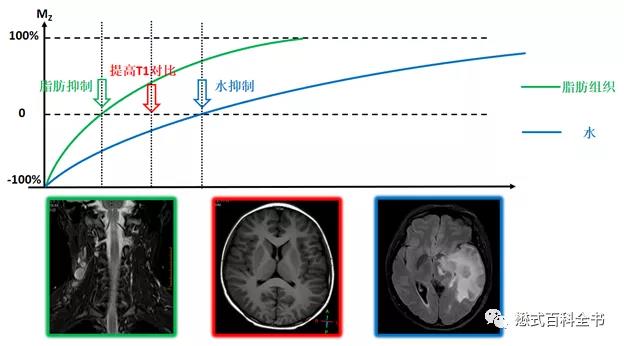

反转恢复序列通过施加一个反转脉冲进行磁化准备可以达到选择性抑制某种组织信号或者提高图像T1对比度的作用。所以该序列的T1对比优于常规的SE序列或TSE序列,这是因为所有组织从负方向开始恢复,拉大了组织之间纵向驰豫的尺度,类似于两个跑步者速度有差别,跑200米路程两人之间的差距要大于跑100米。

用上图来说明IR序列的两个主要作用:选择性的抑制某种组织及增加T1对比。

既然可以施加一次反转脉冲,那么也可以连续施加两个或者多个反转脉冲,然后根据各个反转脉冲之间的间隔时间形成双反转或者多反转序列。